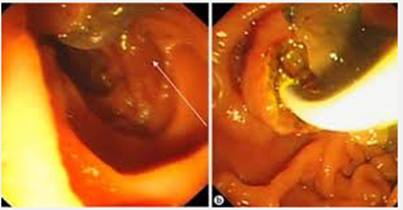

+Hội chứng dạ dày tá tràng do nhiễm giun lươn: hiện tại bệnh lý nhiễm giun lươn ở đường tiêu hóa, nhất là trong khu vực nhiệt đới như Việt Nam, đặc biệt giun lươn có chu trình tự nhiễm nên nếu không điều trị sẽ tồn tại suốt đời trong cơ thể, biểu hiện bệnh đa dạng và phức tạp, thường có hội chứng dạ dày tá tràng kèm rối loạn tiêu hóa. Chẩn đoán bệnh có nhiều phương pháp như nội soi, hút dịch, sinh thiết mảnh mô tìm ấu trùng giun lươn, soi cấy phân (có điểm đặc biệt là người bệnh phải mang toàn bộ số phân đi trong ngày đến phòng xét nghiệm để làm phương pháp tập trung thì may ra tìm ấu trùng được) hoặc phổ biến nhất là kỹ thuật ELISA. Trong số 78 bệnh nhân nghi ngờ nhiễm giun lươn thì tỷ lệ nhiễm tính bằng ELISA là 29,48%, trong khi áp dụng các kỹ thuật chẩn đoán khác như nội soi dạ dày tá tràng tìm ấu trùng giun lươn, soi phân tìm ấu trùng giun lươn hoặc đếm bạch cầu ái toan cao gợi ý cũng cho kết quả phát hiện thấp hơn ELISA;

-Về mặt giải phẩu bệnh, đường mật luôn luôn dãn rộng, đường kính lớn hơn 1,5-3 lần so với bình thường, hay gặp nhất trong các trường hợp tắc đường mật (Khorcandi và cs., 1977), nang nhỏ trong ống mật có thể quan sát thấy đầu tụy to ra và chắc (Maroy và cs.,1987). Nếu tắc mật thì túi mật thường to ra, phù nề, kích thước có thể đến 7 x 12 x 7cm, bờ dưới có thể sa đến ngang rốn (Chen và Mott., 1990). Xơ hóa túi mật với các tổ chức lân cận rất thường thấy, sỏi ống mật hay túi mật cũng hay gặp, thường là sỏi nhỏ và số lượng sỏi nhiều (Wong và cs., 1985; Chen và Mott., 1990; Arjona và cs., 1995). Thành phần bên trong đường mật và túi mật có thể chứa hỗn hợp máu, dịch mật, cặn máu đông và cặn sơi tơ huyết fibrin, chất mụn nát, đôi khi có cả mủ và máu trộn lẫn (Huỳnh Hồng Quang và Lê Quang Quốc Ánh., 2005);